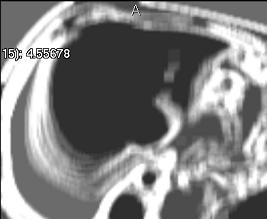

Deviation (simple)

../../../Modules/ML/MLFilter2/mhelp/Images/TextureFilterImages/deviation.jpg